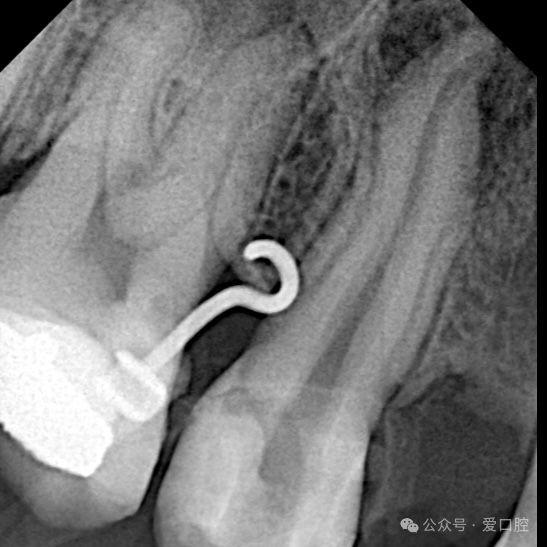

影像学检查:小牙片示:15冠部高密度影,根管内可见高密度影像,牙周膜增宽影,根尖低密度影。CBCT示:15遗漏腭侧根管。

15,安放橡皮障隔离后,显微镜下,开髓,暴露髓腔内牙胶,去除髓腔内牙胶,探查颊侧根管,使用再治疗镍钛锉去除根管上段牙胶,8号k锉,10号k锉疏通至根尖,3%次氯酸钠溶液冲洗,根测长度为19mm,3%次氯酸钠溶液冲洗,探查腭侧根管,发现髓室顶未揭干净,有牙胶残留,揭净髓室顶,去净残留牙胶,疏通腭侧根管至根尖,3%次氯酸钠溶液冲洗,根测长度为19mm,镍钛预备至3504,试尖, 3%次氯酸钠溶液冲洗, Eddy荡洗(20秒3次),蒸馏水冲洗,17%EDTA溶液冲洗,蒸馏水置换,吸干,氢氧化钙封药,玻璃离子暂封。